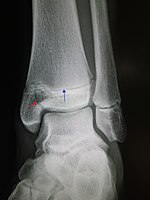

Segond fracture Paul Segond lateral tibial plateau avulsion fracture with anterior cruciate ligament tear Segond fracture at Who Named It? SegondFracture.JPG